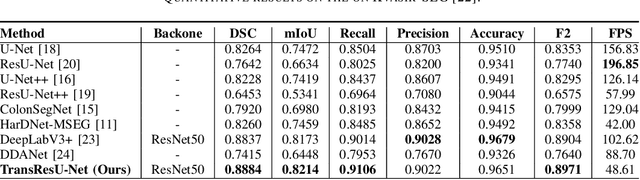

TransResU-Net: Transformer based ResU-Net for Real-Time Colonoscopy Polyp Segmentation

Jun 17, 2022

Colorectal cancer (CRC) is one of the most common causes of cancer and cancer-related mortality worldwide. Performing colon cancer screening in a timely fashion is the key to early detection. Colonoscopy is the primary modality used to diagnose colon cancer. However, the miss rate of polyps, adenomas and advanced adenomas remains significantly high. Early detection of polyps at the precancerous stage can help reduce the mortality rate and the economic burden associated with colorectal cancer. Deep learning-based computer-aided diagnosis (CADx) system may help gastroenterologists to identify polyps that may otherwise be missed, thereby improving the polyp detection rate. Additionally, CADx system could prove to be a cost-effective system that improves long-term colorectal cancer prevention. In this study, we proposed a deep learning-based architecture for automatic polyp segmentation, called Transformer ResU-Net (TransResU-Net). Our proposed architecture is built upon residual blocks with ResNet-50 as the backbone and takes the advantage of transformer self-attention mechanism as well as dilated convolution(s). Our experimental results on two publicly available polyp segmentation benchmark datasets showed that TransResU-Net obtained a highly promising dice score and a real-time speed. With high efficacy in our performance metrics, we concluded that TransResU-Net could be a strong benchmark for building a real-time polyp detection system for the early diagnosis, treatment, and prevention of colorectal cancer. The source code of the proposed TransResU-Net is publicly available at https://github.com/nikhilroxtomar/TransResUNet.